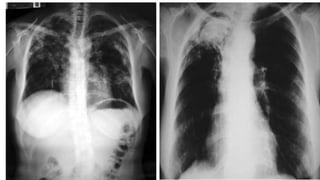

 Rx tipica

• Imagen radiologica de aspergiloma

Aspergilosis Pulmonar Formas clínicas: Broncopulmonaralergica:  Broncoespasmo paroxistico.  Eosinofilia Aspergiloma: “bola fungica”:  Hemoptisis  Rx tipica Masiva diseminada:  Amenaza la vida, en Inmunodeprimidos.  Fiebre  Tos  Disnea  Dolor Toracico Pleuritico.